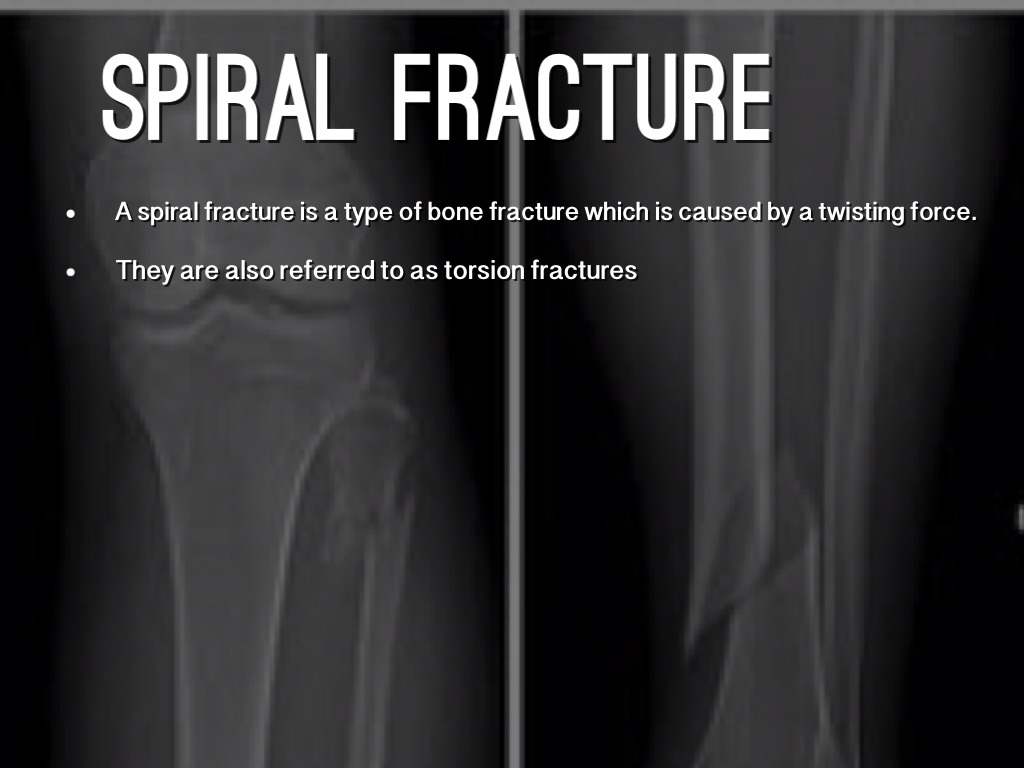

SPIRAL FRACTURE

A spiral fracture is a type of bone fracture which is caused by a twisting force.

They are also referred to as torsion fractures